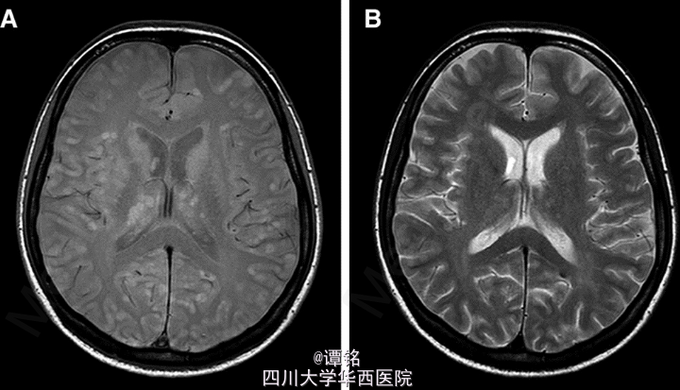

克唑替尼治疗 6 个月后,患者出现了疲劳,发音困难,抑郁和紧张。增强 CT 未见脑部转移病灶,而胸部病灶继续缩小。然而,头颅磁共振显示除灰质外,大脑皮质,基地核和丘脑 ( 图 2A 和 B) 出现了粟粒状结节。T2 质子加权相表现为小的高信号结节(2-7mm),一些转移灶中表现为弥漫性 DW1 信号和 ADC 图像。